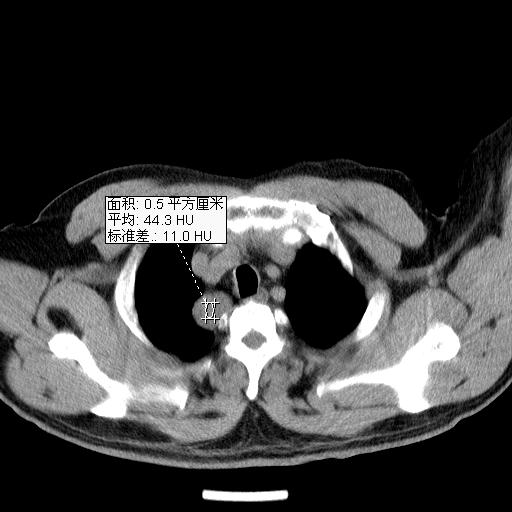

男,51岁,体检时发现右上纵隔高密度影。

右上纵隔脊柱旁圆形结节,密度均匀,边界清楚——考虑神经源性肿瘤!